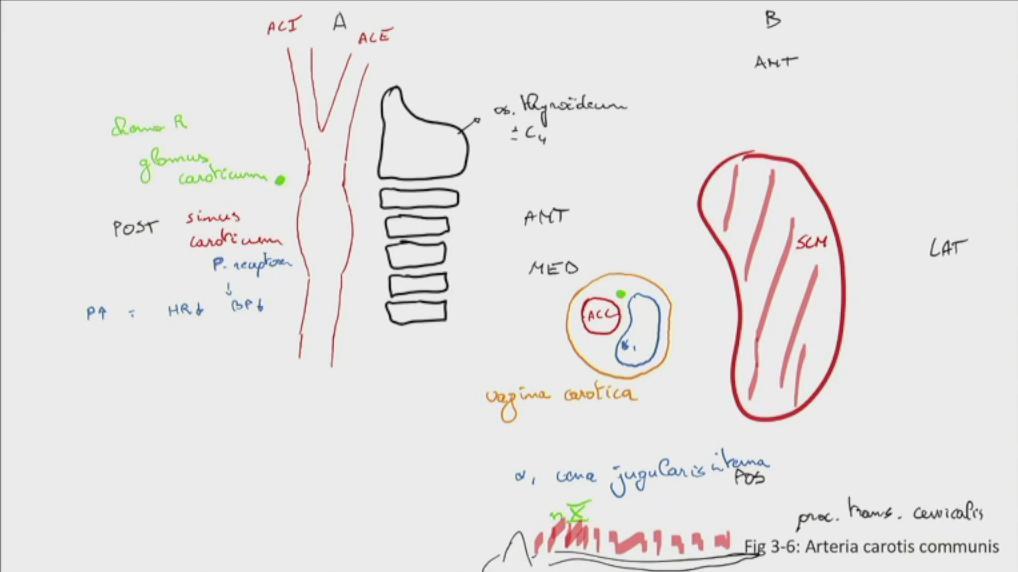

Fig 3.06: a. carotis communis

A zijaanzicht

os thyroideum? t.h.v. C4 a carotis communis (ACC) a carotis externa (ACE) a carotis interna (ACI) -

sinus caroticus

-

glomus caroticum

t.h.v. bifurcatie bevat chemoreceptoren

B doorsnede

m sternocleidomastoideus (SCM) posterieur: cervicale wervels > proc. transversus + pre-vertebrale spieren -

mediaal: vagina carotica

a carotis communis v jugularis interna n vagus (X)